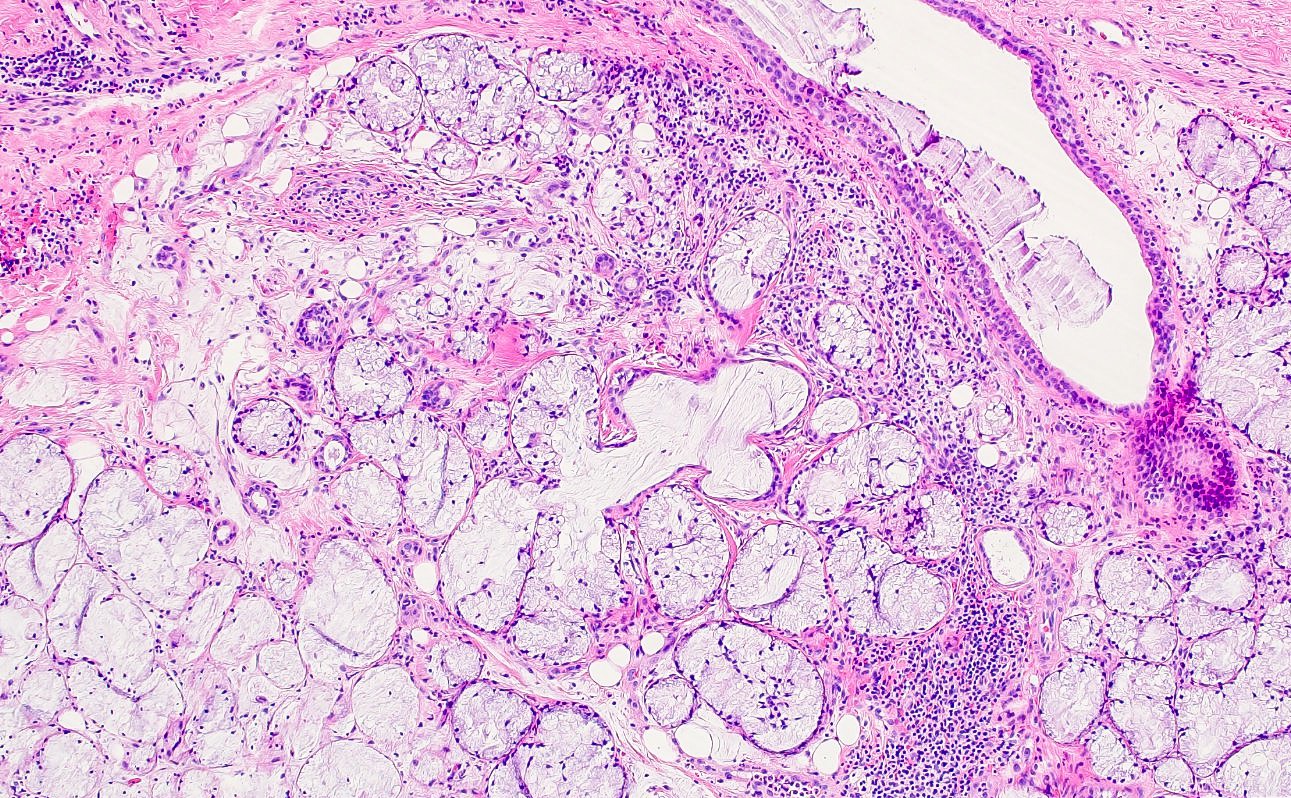

Microscopic (histologic) description

- Squamous metaplasia of ductal structures and acini with preservation of the salivary lobular architecture is an essential feature, according to World Health Organization (see WHO classification-oral cavity & oropharynx)

- Necrosis / infarction of acini characterized by loss of nuclei and cell borders with or without zones of spilled mucin

- Pseudoepitheliomatous hyperplasia with generally bland cytology or keratinocytic regenerative atypia

- Reactive, myxocollagenous background stroma

- Surface ulceration, granulation tissue and subacute inflammation may be present

- Has been conceptualized by 5 histologic stages of development and evolution: infarction, sequestration, ulceration, repair and healing (Int J Oral Surg 1982;11:283)

Microscopic (histologic) images